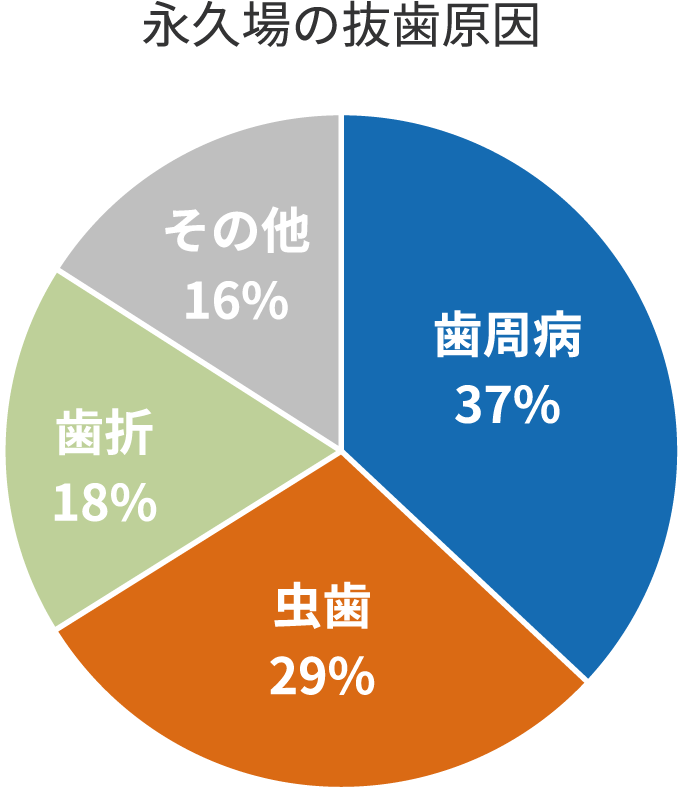

日本人が歯を失う原因で最も多いのが歯周病です。

発症すると自然に治ることはなく、重度の場合は抜歯になってしまうことも少なくありません。